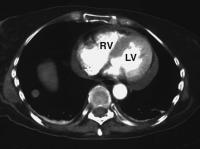

Abbildung 3: Computertomographie: Auch in der Computertomographie findet sich ein auffallend unregelmäßig begrenztes Myokard; LV = linker Ventrikel; RV = rechter Ventrikel, zusätzlich intrapulmonale Rundherde.